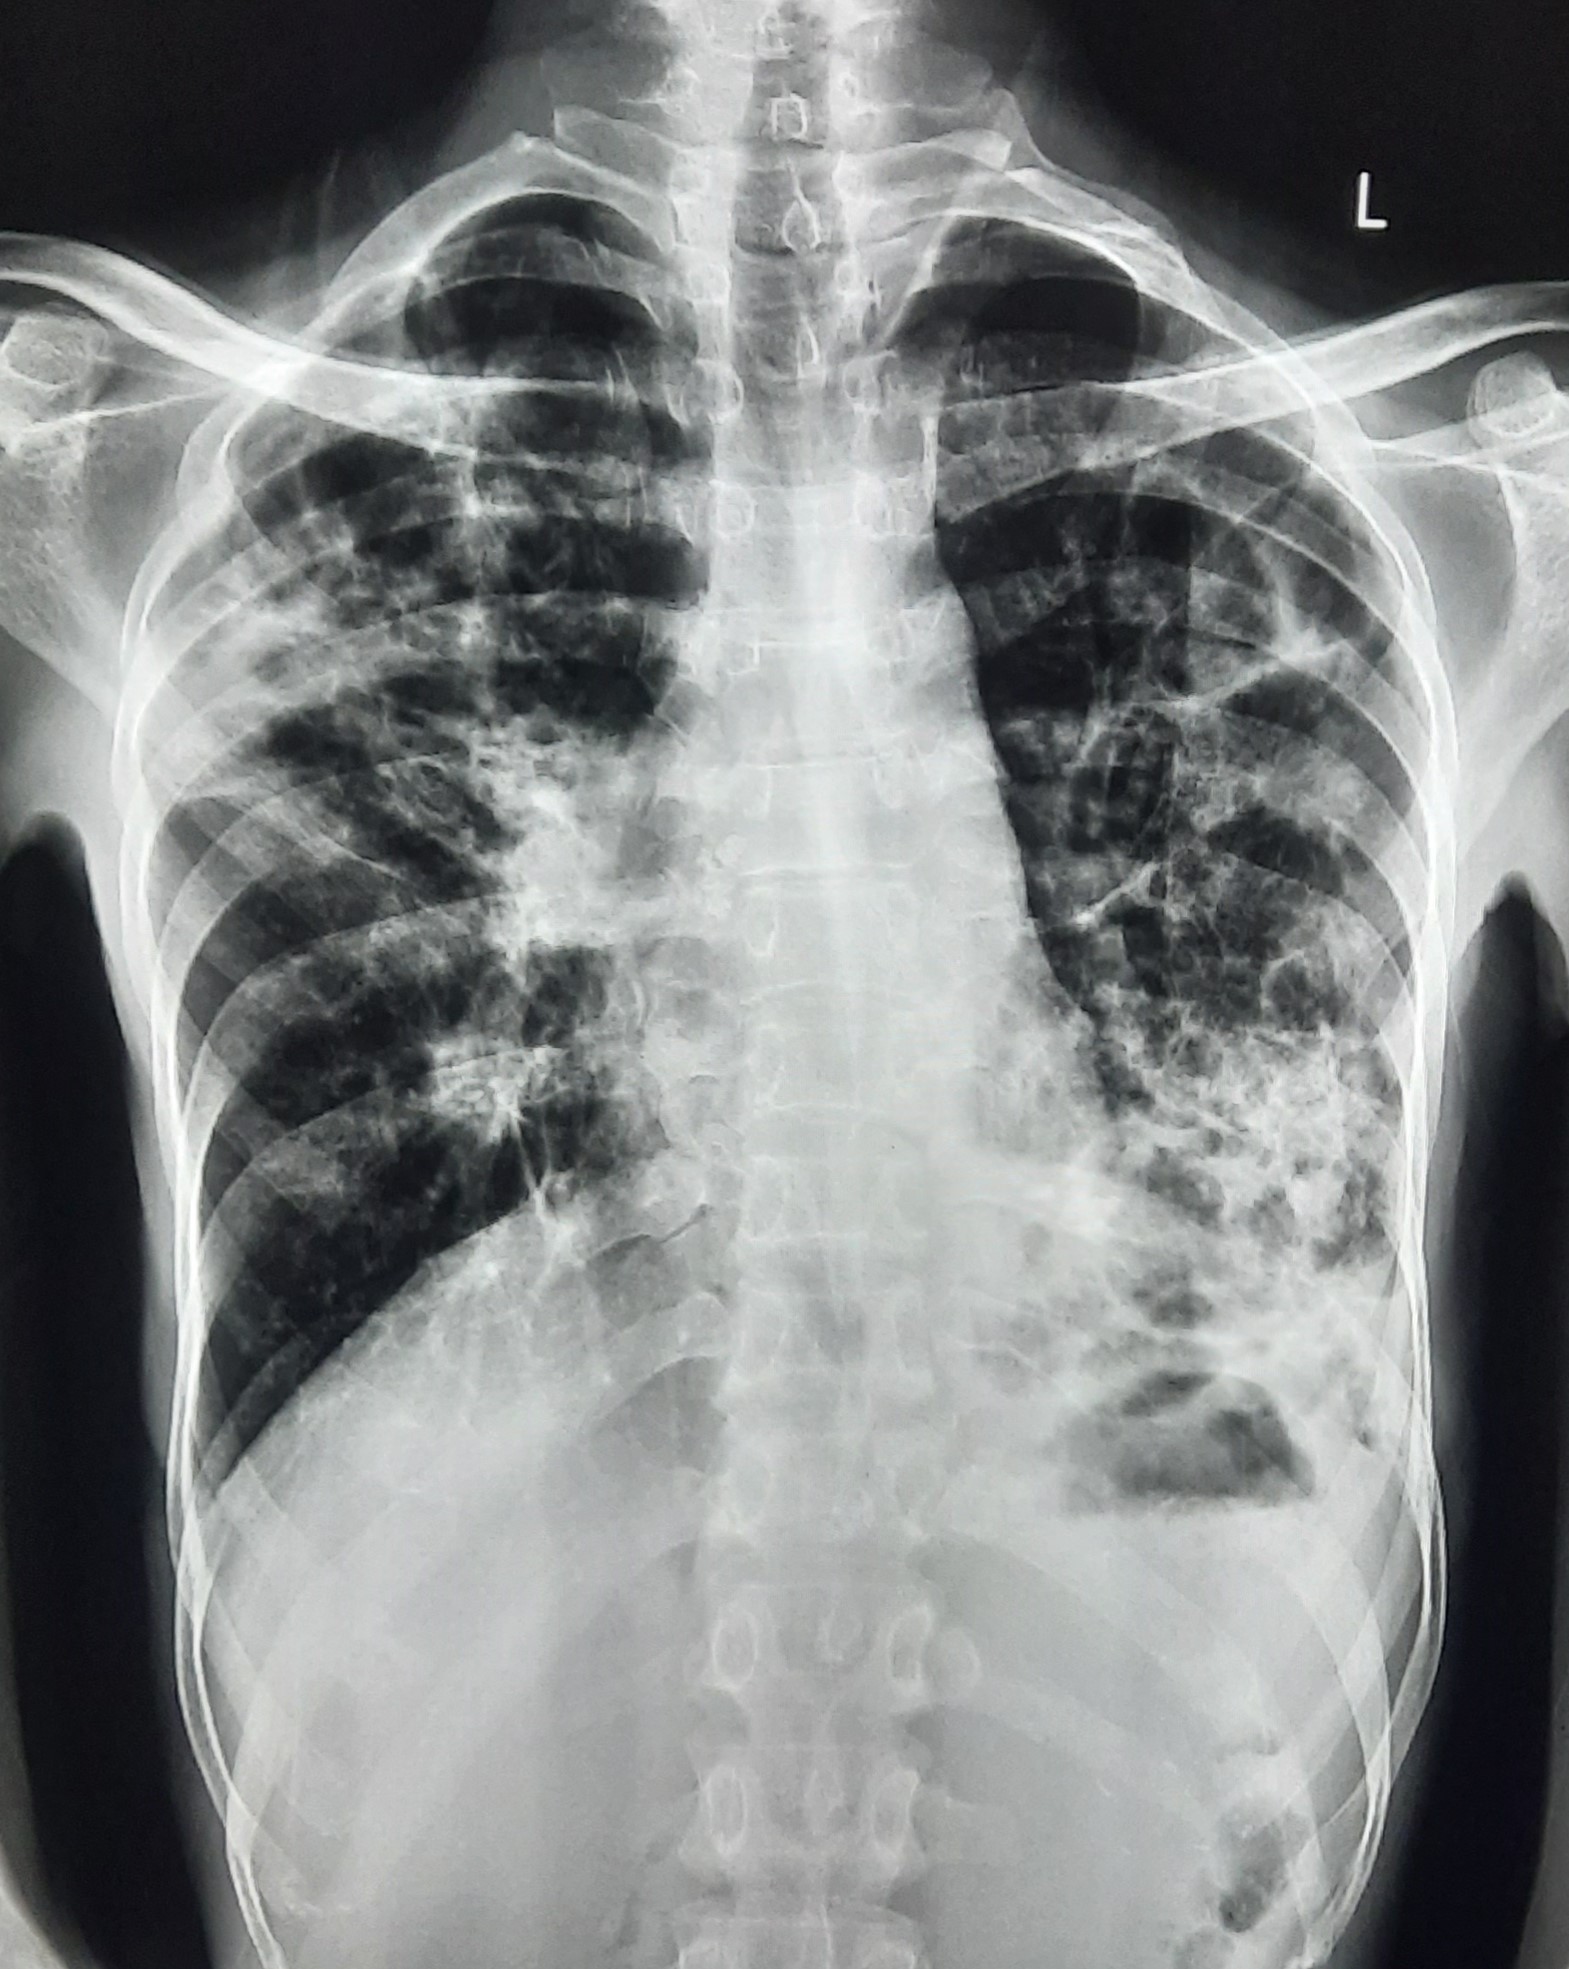

| 132 | IGGMC, Nagpur, Nagpur | P2 | 29-4340 | Ritesh Chaudhary | Consent taken on Paper | 30 Yrs. |

Provisional Diag : Post TB Sequelae

Final Diag : Post TB sequalae With Fibro Cavitary Changes |

Post TB Sequelae | Bilateral Upper Zone Fibro Cavitary Changes With Right Upper Zone Fungal Ball With Bilateral Haziness With Tenting Of Diaphragm | Abnormality visible on x-ray |